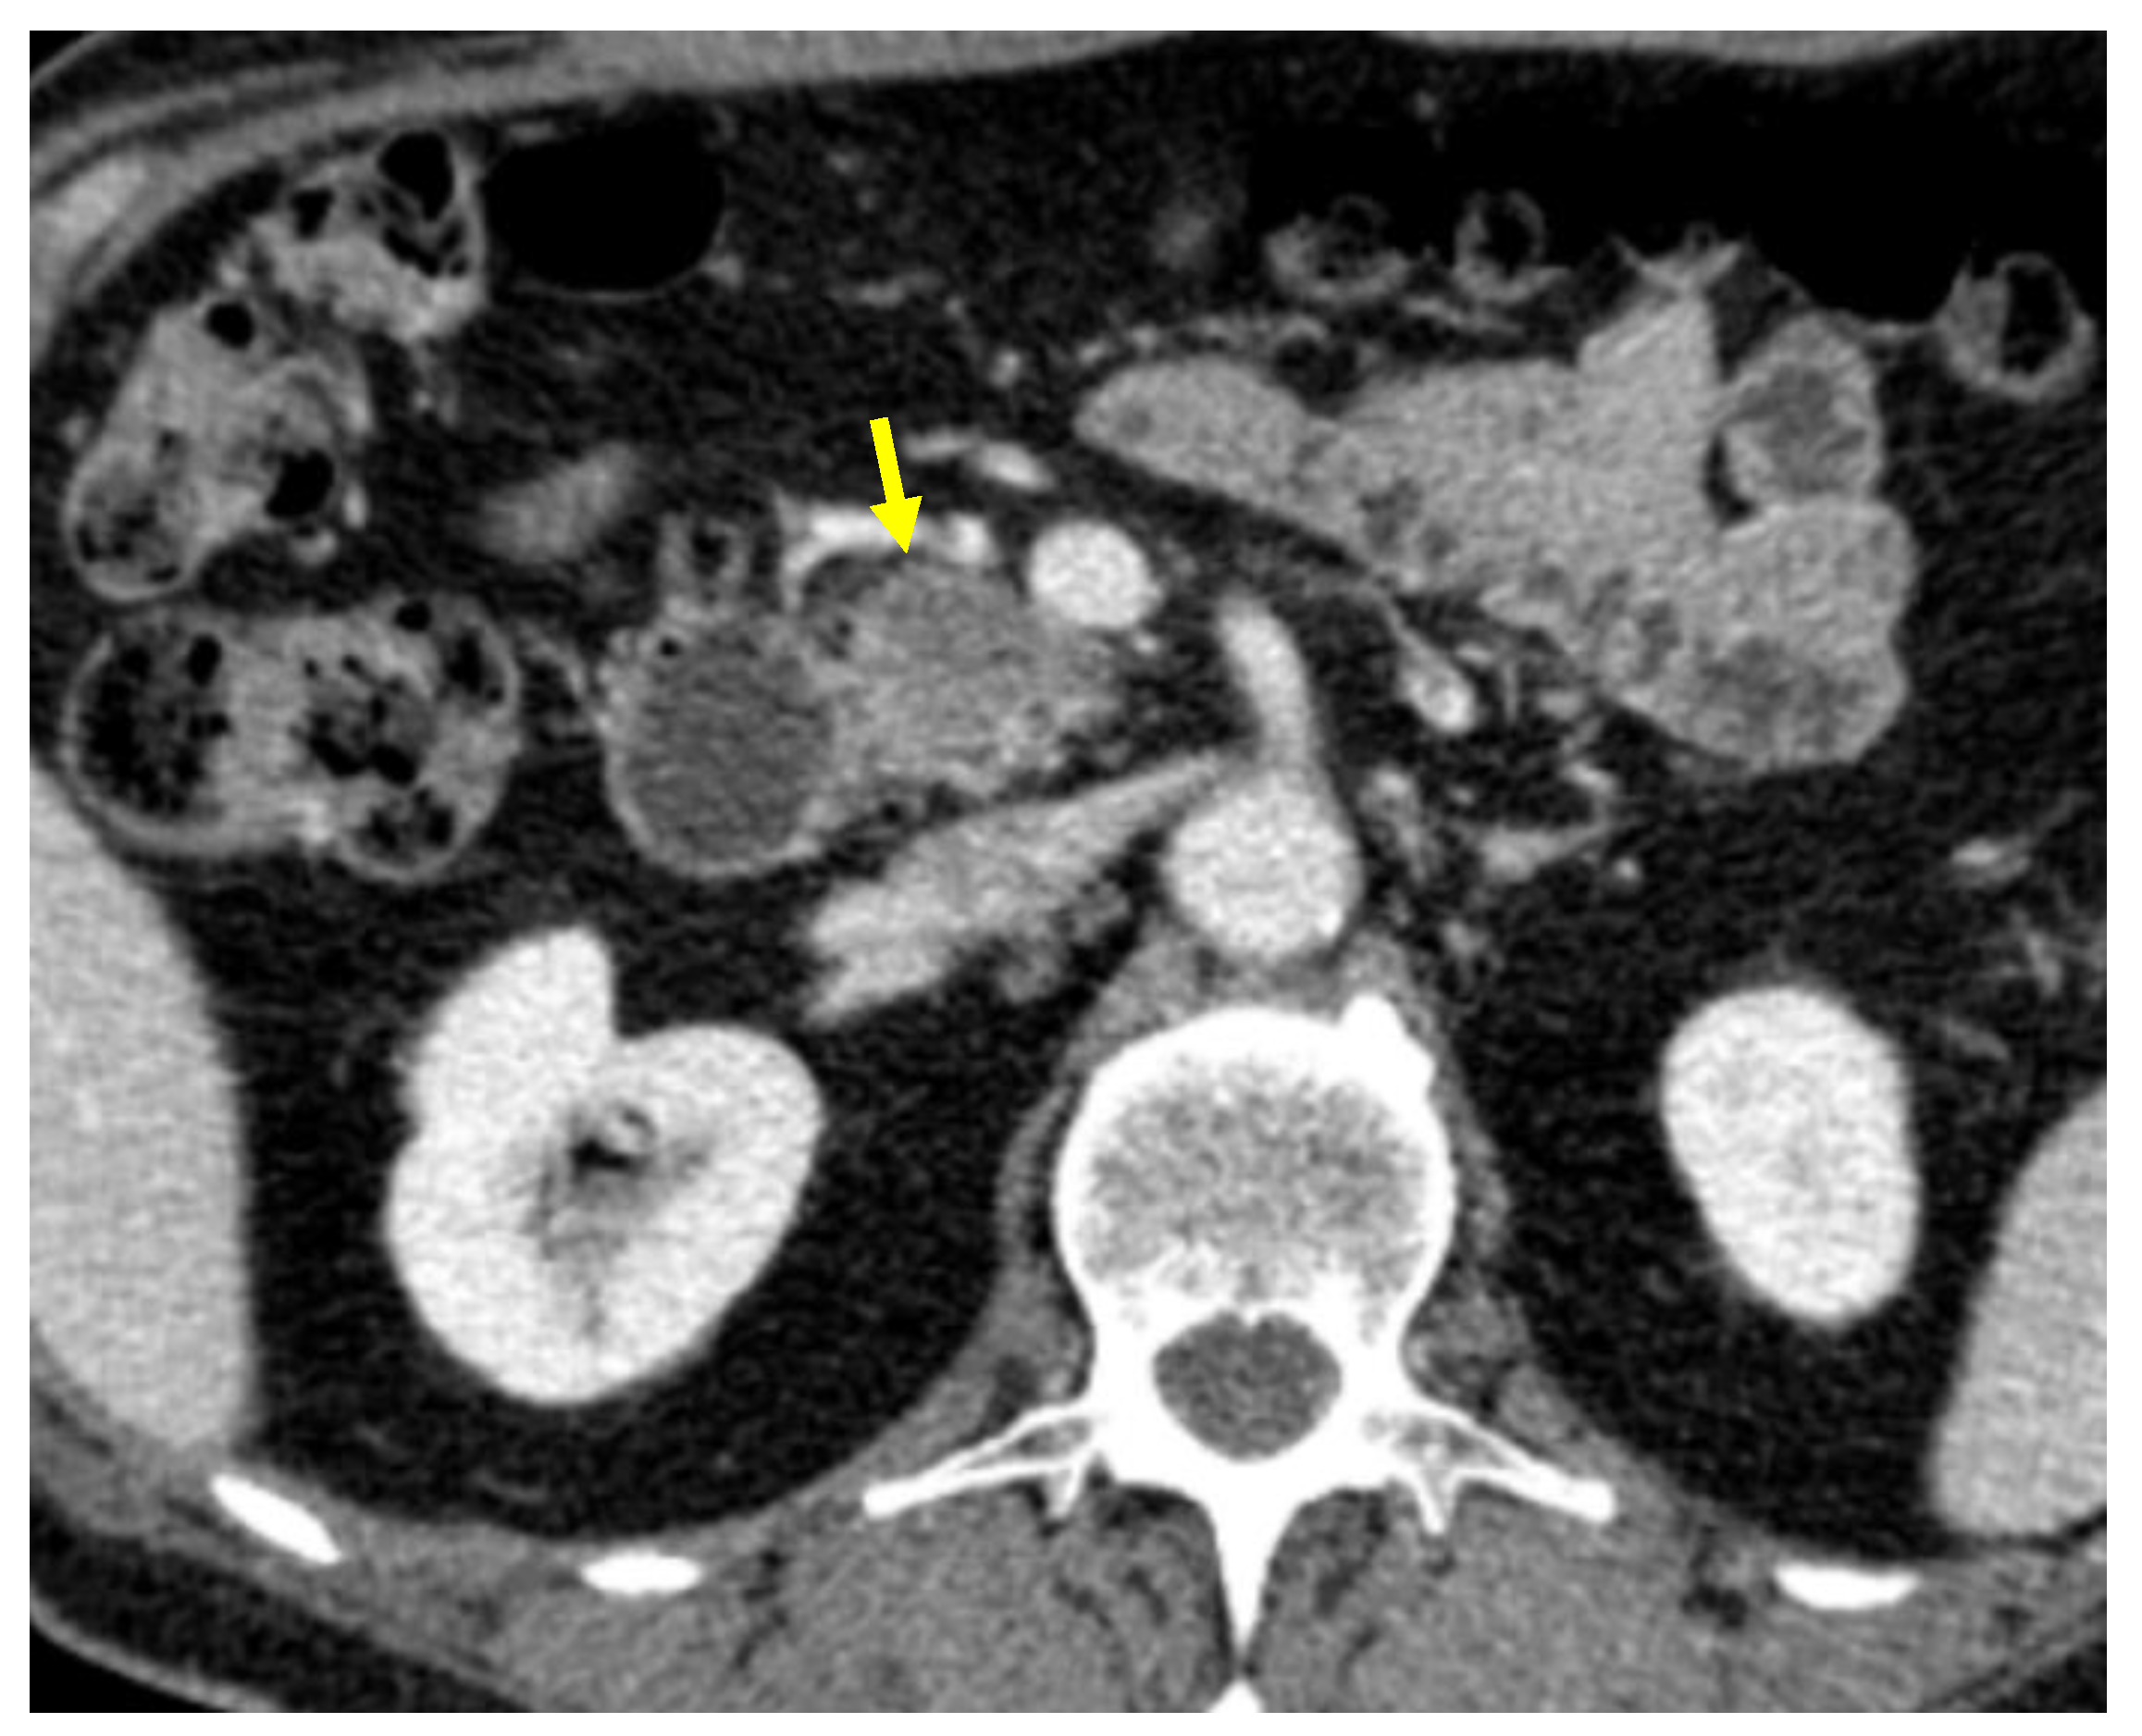

Tumor margins showed a significant difference in the two groups, appearing well-defined in only 6 (6.98%) metastatic patients and ill-defined in the remaining 80 (93.02%); in the non-metastatic group, the margins appeared well-defined in 132 (65.35%) and ill-defined in 70 (34.65%) tumors (Figure 2, Figure 3, Figure 4 and Figure 5).

Figure 5. Pancreatic lesion with ill-defined margins (arrow) on CT examination in portal-venous contrast phase.